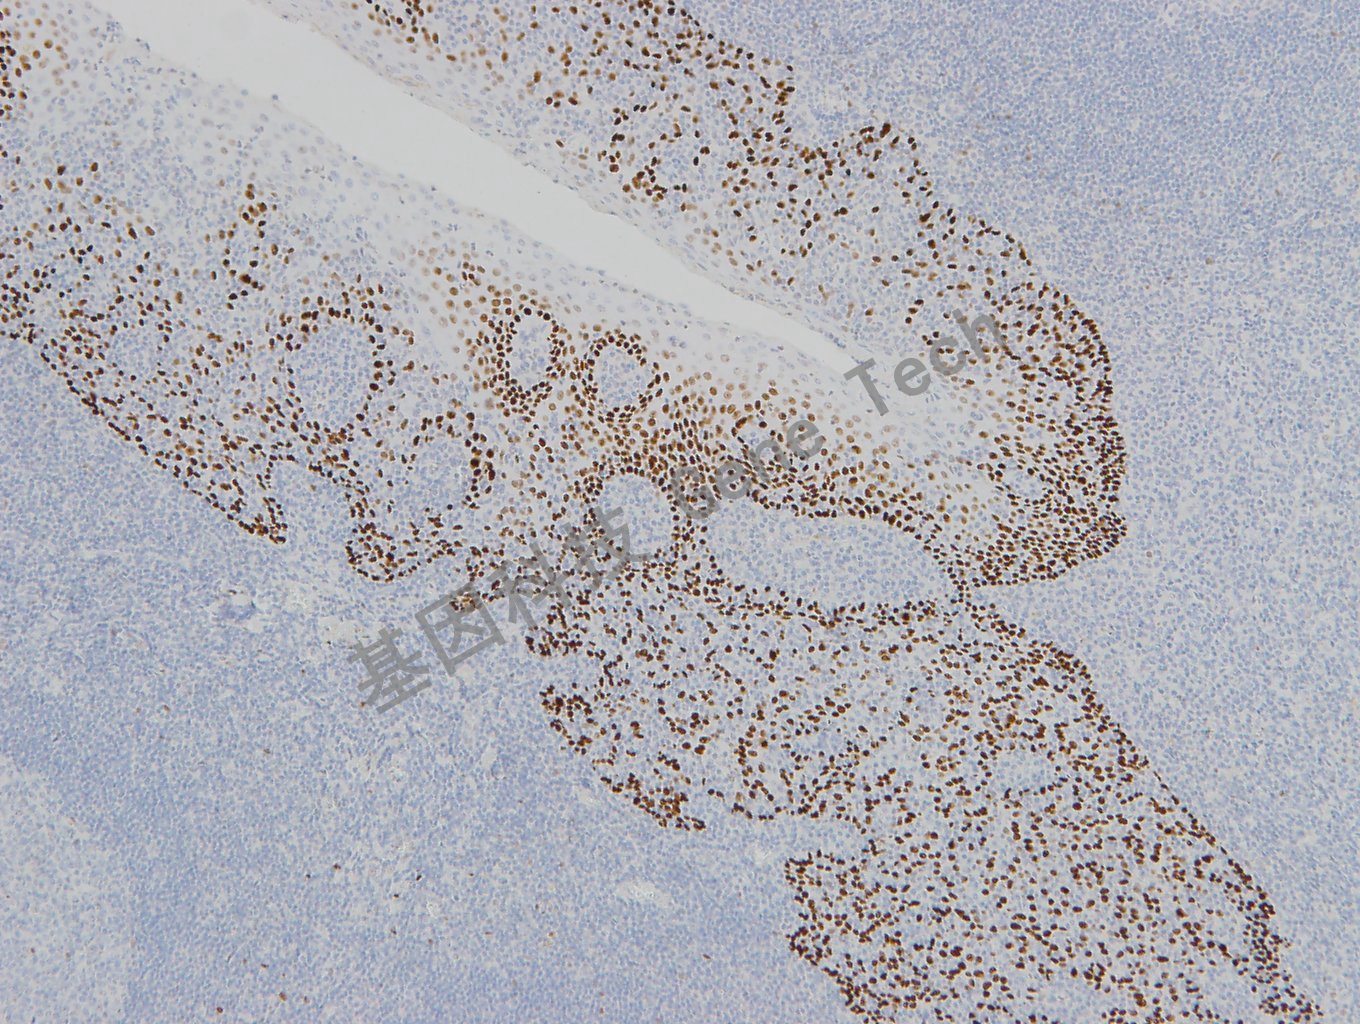

p63 兔抗人 p63 抗體試劑(免疫組織化學(xué))(GR004)

| 預(yù)處理:高pH熱修復(fù) | 陽性部位:細(xì)胞核 | 陽性對(duì)照:前列腺 |

| 扁桃體石蠟切片,用 p63(GT2331)染色,細(xì)胞核陽性,DAB 顯色。 | ||